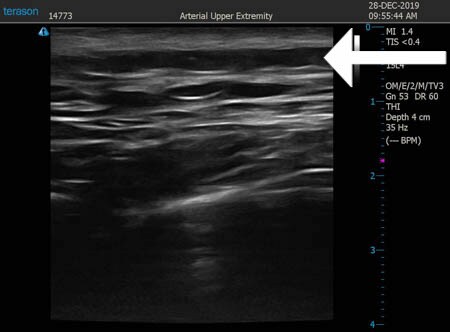

いつものように3Dタッチビュー(超音波)で

皮下脂肪層を評価してみましょう。

左肩甲骨横

↓ ↓ ↓

上の画像の部分の皮下脂肪層をつまんでみましょう。